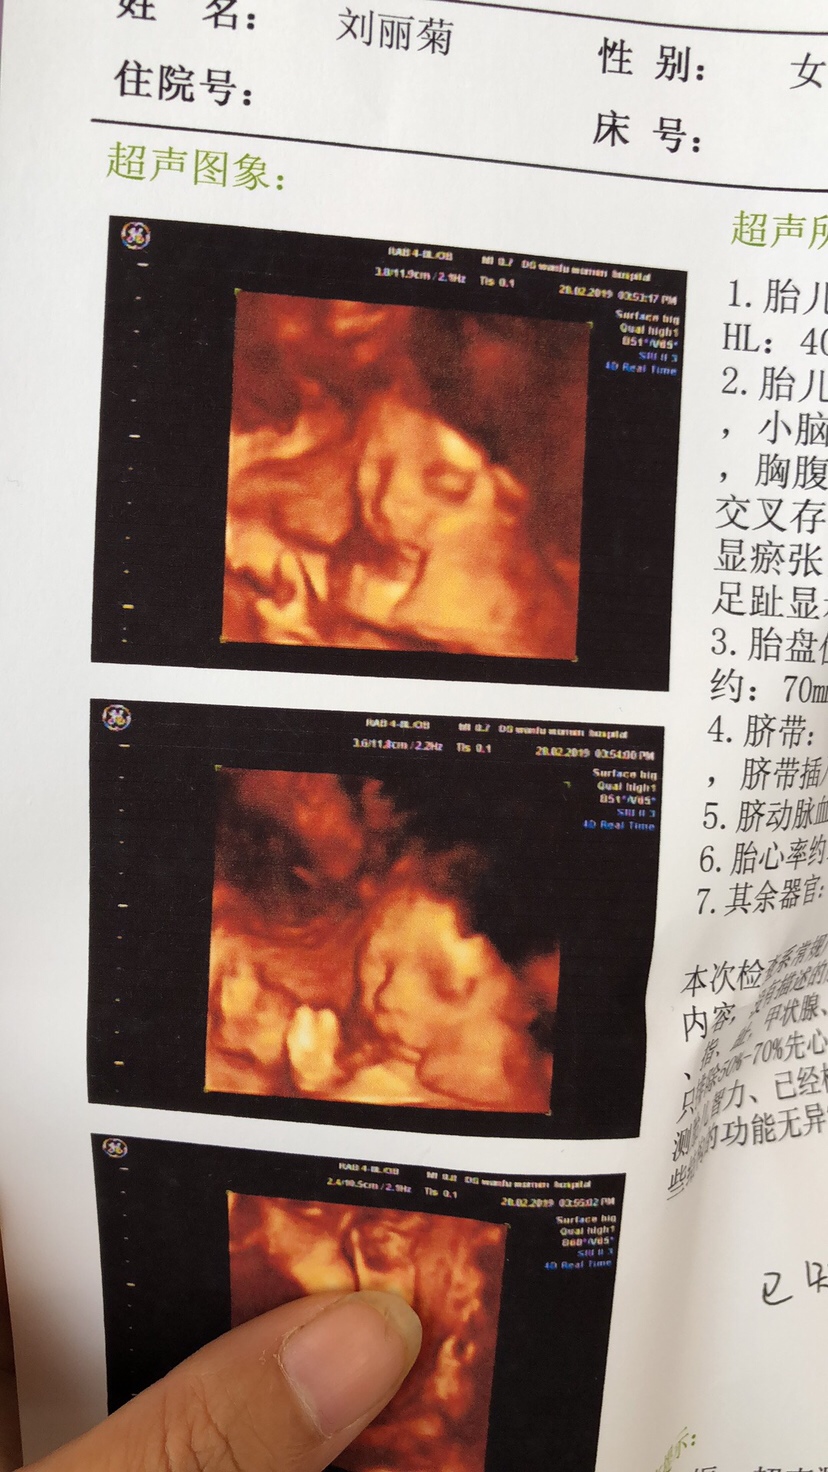

孕22周+0天

真的,好像是男宝宝呀